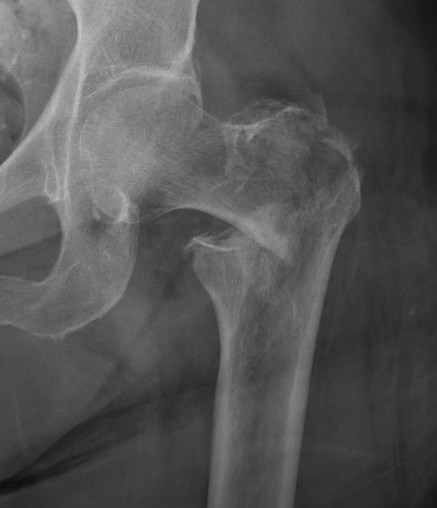

Type II Reverse Oblique Type

Inherently unstable - tendency of femoral shaft fragment to shift medially

Reverse oblique fractures

Stability

Depends on medial cortical reduction

Unstable (AO 31.A2 + 31.A3)

- intact lateral wall

- posteromedial cortical fracture

- reverse oblique

- subtrochanteric extension